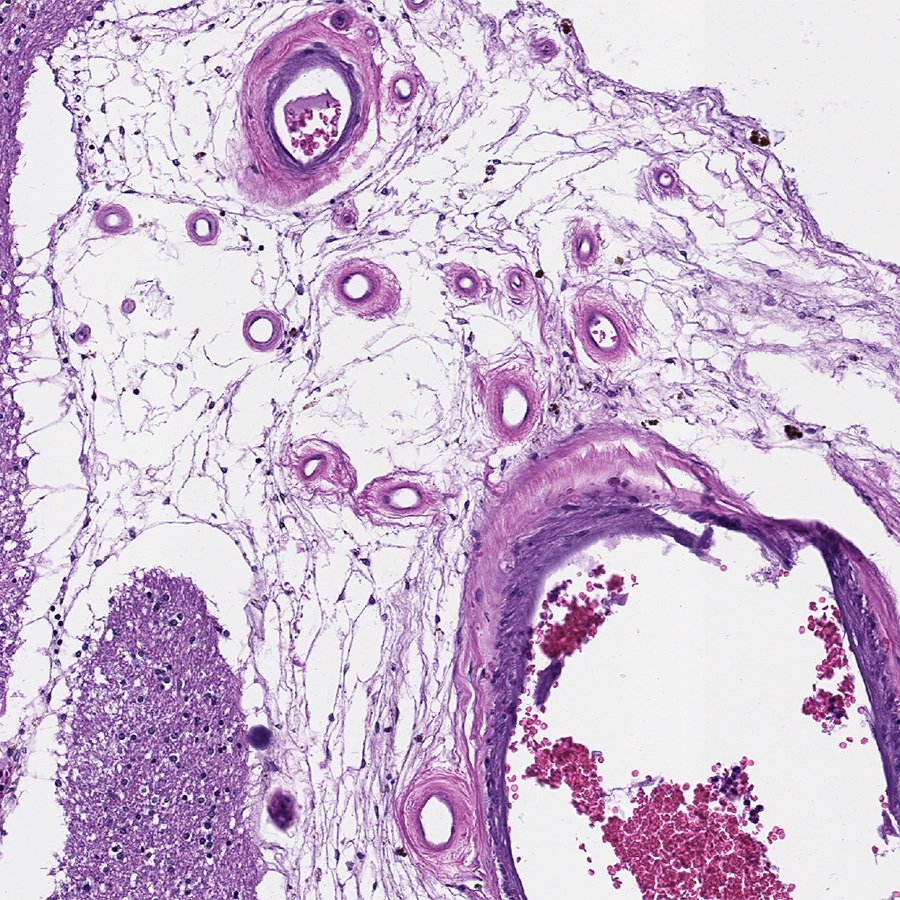

This is subcortical arteriosclerotic encephalopathy, a.k.a. Binswanger's Disease. Resembles

#Alzheimers clinically, but it's caused by bad#arteries.#Exercise and healthy diet are your best protection!#pathology#neuropath#pathtwitterpic.twitter.com/bgE5j6hV8y